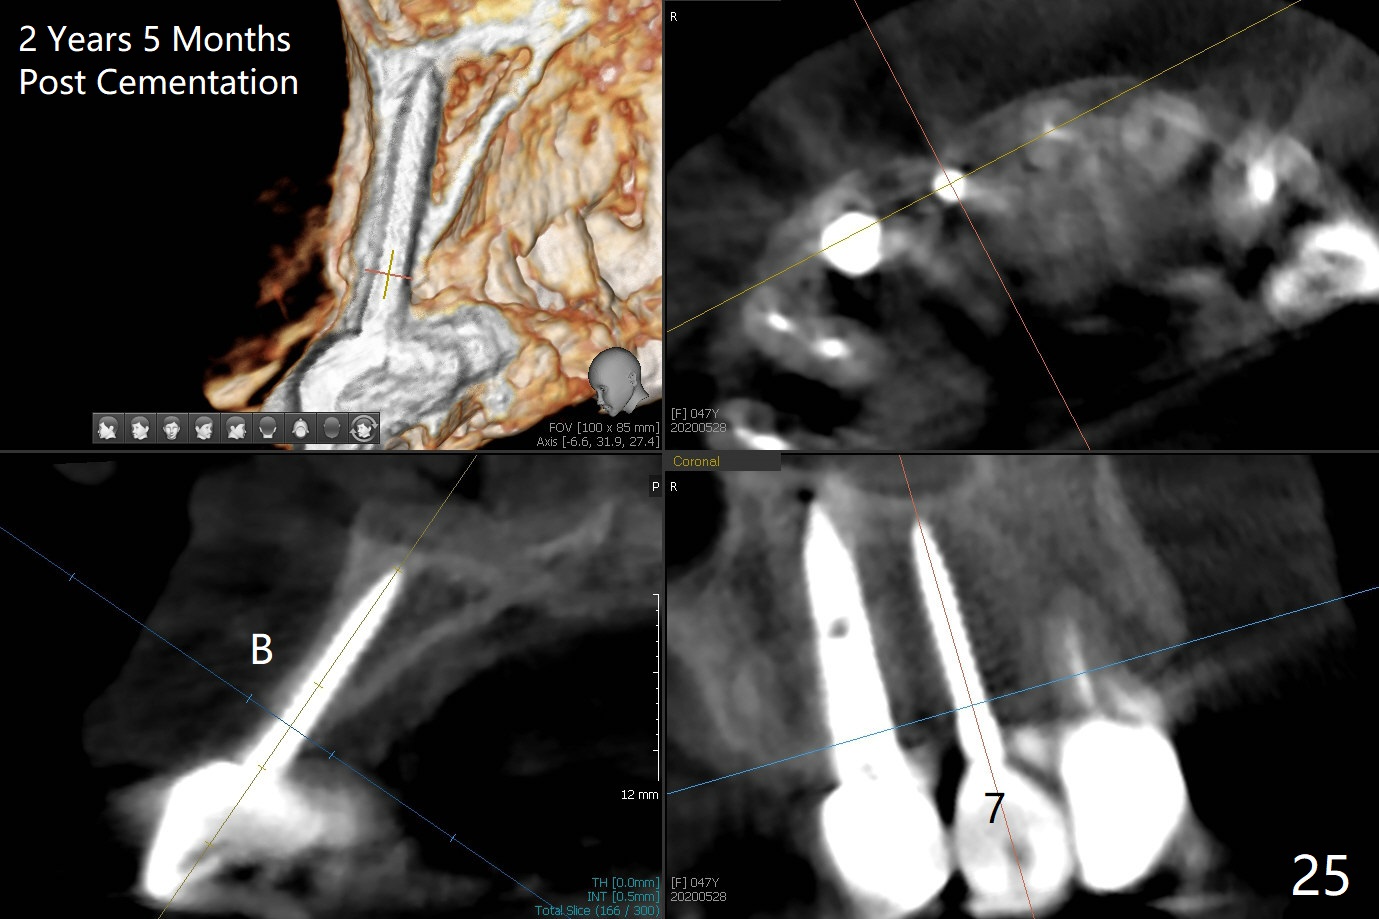

Since the ridge at #7 is ~ 4 mm, a 2.5x14 mm 1-piece implant is placed (Fig.8) after 1.2 mm (Fig.7), and 1.5 mm drills at 12 mm and 2 mm drill at 8 mm.  Later the implant is placed deeper (Fig.10).  There is no bone loss 7 or 12 months postop, respectively (Fig.11,12).  After Diode gingivectomy, there is papillary formation (Fig.13).  No provisional is provided after impression (with the abutment torqued at #6) for oral hygiene.  With access holes at #6 and 7, crowns are bonded with minimal residual cement (Fig.14 <, which is removed later).  There is no hard (Fig.15,16) or soft (Fig.17 *) atrophy 26 months postop, i.e., 13 months post cementation, due to the presence of socket shield (Fig.15 <, as compared to Fig.1).  In fact the tooth #8 has mobility and fremitus (short root/poor crown/root ratio, Fig.16); occlusal adjustment is done 13 months post cementation.  The crown is dislodged 2 years 1 month post cementation; a prefabricated post is being tried in (Fig.18).  There is no atrophy, bone loss or infection at #6 (with socket sheath (*)) or 7 two years 5 months post cementation (Fig.20-27).